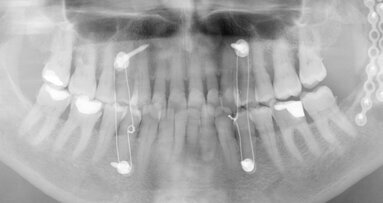

(Image: Kuraray Noritake Dental)